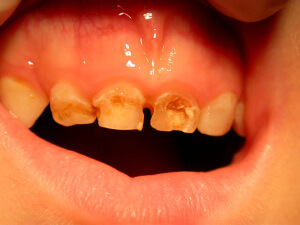

Caries

Caries is a disease. It is the most widespread disease in the world. The bacterial dental plaque (also called a biofilm) is the main cause of the infection of the teeth and the supportive tissues, i.e. of the caries and periodontal diseases respectively. The accumulation of dental plaque and the colonization of bacteria lead to the appearance of dental and periodontal pathology.

Microbes cling on various surfaces and form the biofilm. In addition, frequent intake of carbohydrates (especially sweets) gets metabolized to acids. The pH of dental plaque becomes acidic repeatedly, and that favors acid tolerant bacteria, such as streptococci and lactobacilli that are the most dangerous bacteria for caries.

Research shows that caries as a disease is identified at certain groups of people that are more prone to it. 80% of the carious cavities are located on 20% of the world’s population.